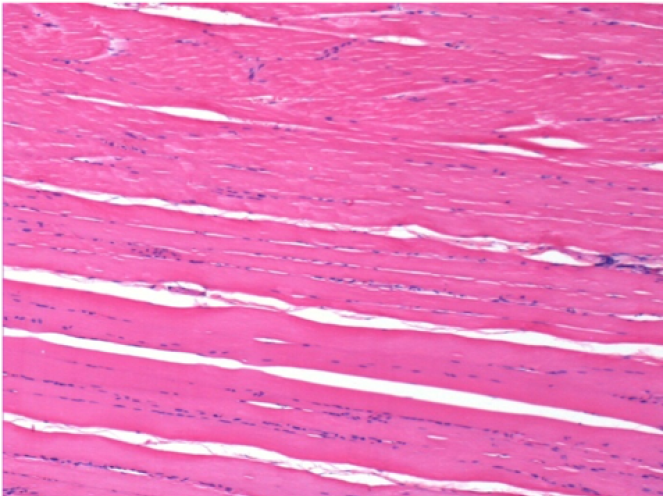

7 mesi dopo Iniezione di Endopeel

Scatola Nr 5

7 mesi (Giorno210) dopo iniezione IM di 0.1ml di Endopeel nel muscolo pretibiale destro ( Dx).

Restitutio ad integrum completo dopo 7 mesi

Sx : Controllo-100x-Giorno210

Dx:100x-Giorno210

Sx :Controllo 50x-Giorno210

Dx:50X-Giorno210